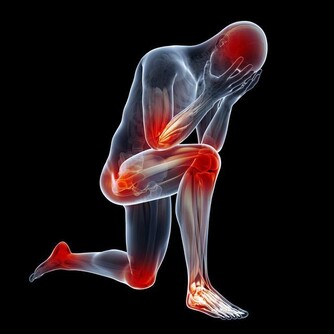

但傷害他們的,不是血管出血破裂,而是來自心臟的血栓阻斷了血液流通。

林口長庚神經外科醫師王以舟表示,

過去治療血栓,通常是以發病3小時為基準,注射靜脈血栓溶解劑,

一旦超過黃金時間或是­血栓纖維頑強無法消除,就會進入消極的傳統復健治療,

但隨著技術進步,新型介入性動脈­機械取栓法,

不僅將治療黃金期延長至12小時,更能有效地取出血栓,

前提是,病患大腦­不能全無側枝循環。